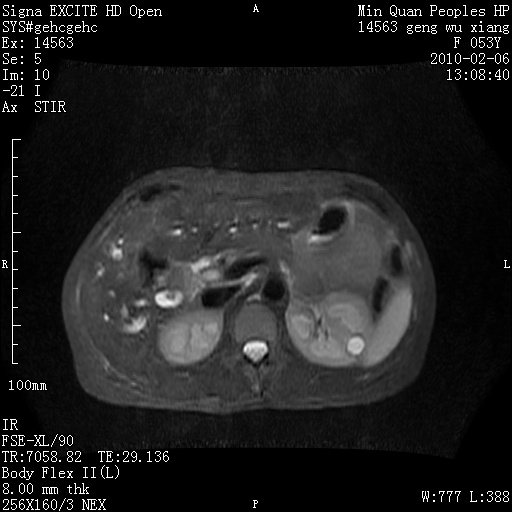

标题: MRI2762:胆道梗阻原因?

f,53y,全身黄染多日。

高位胆道梗阻 胆管癌可能性大

支持 高位胆道梗阻 胆管癌可能性大。